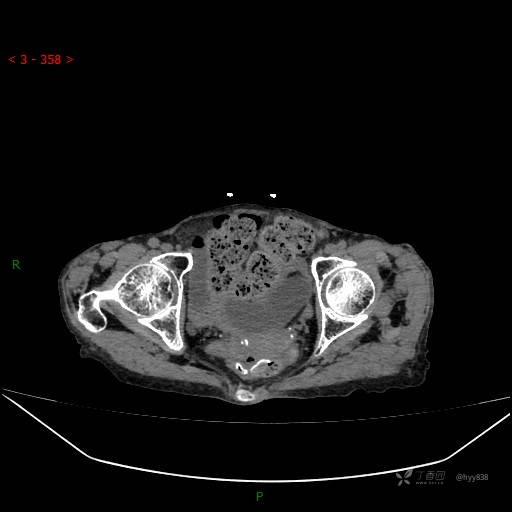

夜班急诊经典病例分享。老年女性,突发腹痛就诊,请讨论……结果公布~

主诉 :腹痛14小时

现病史: 家属诉患者于14小时前出现腹痛,伴有肛门停止排气排便,不伴有畏寒、发热、恶心呕吐、腹泻等不适,患者家属为求进一步治疗,就诊于我院急诊科,门诊以腹痛待查收入院, 起病以来,患者精神、睡眠差,进食少,小便正常,大便未解,近期体力、体重无明显下降。

腹部CT平扫